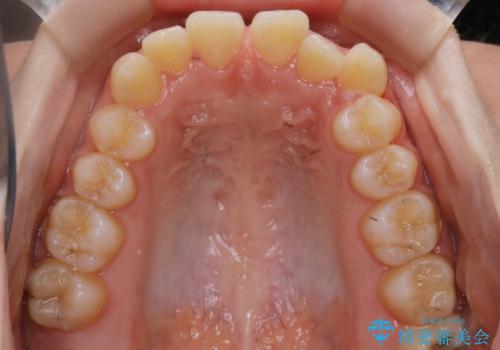

【非抜歯】すきっ歯と噛み合わせの治療

- 上の前歯のすきっ歯と下の前歯のガタつきを主訴にご来院されました。

噛み合わせの改善も同時に進めつつ、主訴の部分も効率的に治していくためマウスピース装置でゴムかけを行いながら治療を進めていきました。

正中離開(すきっ歯)

真ん中の歯が左右に開いてしまい隙間ができてしまう状態を「正中離開」といい、俗にすきっ歯と呼ばれています。

隙間を埋めていく方向に歯を移動させることで改善していくケースが多く、比較的治りやすい不正咬合のひとつとされています。

しかしながら、歯が捻じれていたり、噛み合う歯との位置関係によっては治療が難しくなる場合があります。